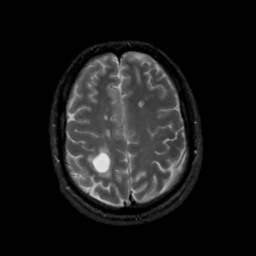

MR Study #8, March 31, 1991 -- Slice #38